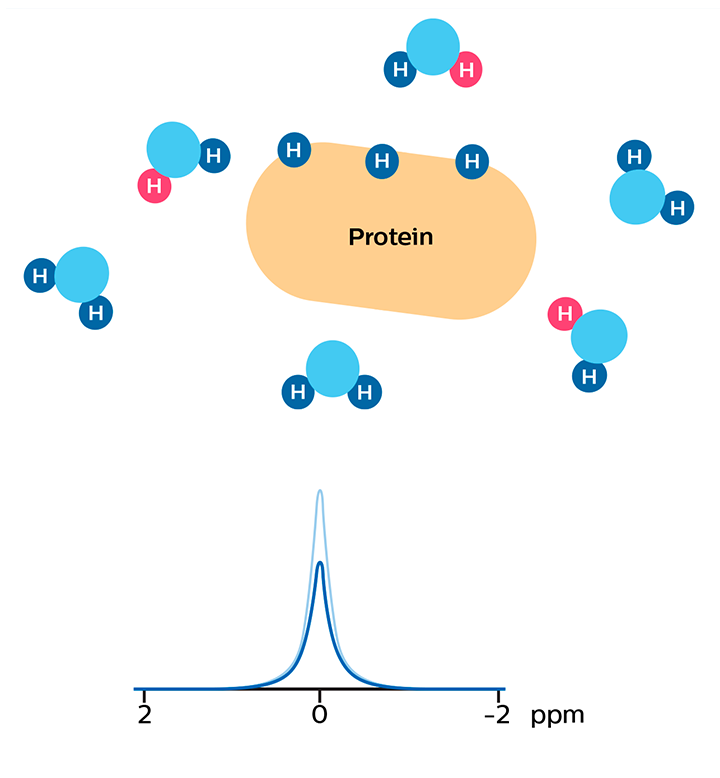

In APT weighted imaging and other CEST methods, the MRI signal is generated by a mechanism different from that of basic MRI. These CEST techniques are based on the chemical exchange of hydrogen atoms. The signal of amide protons of peptide bonds in proteins is too low to be measured in normal MRI. The hydrogen (proton) exchange between protein amide groups and surrounding water allows a different way to measure these amide protons. In APT a narrow RF prepulse (saturation pulse) at the amide hydrogen’s frequency is given to attenuate its MR signal. Because the amide group and water continually exchange hydrogen atoms, the number of saturated protons will build up in water, so that the measured water signal will become lower. The change of the MRI signal of water provides an indirect way to measure the presence of amide. APT images are usually presented as color maps, created by using an asymmetry calculation so that presence of APT is shown as a positive colored signal.

As a result of chemical exchange the nulled protons move from the protein to water molecules.

MR signal of water is reduced due to the proton exchange. In APT, this signal change is used to calculate an APT map that is sensitive to the concentration of the protein.

Studies have shown that the APT signal correlates with the concentration of a protein that is related to cell proliferation. The concentration of this protein, and thus the APT signal strength responds to the grade of malignant tumors.[5-7] APT contrast can potentially highlight tumors that wouldn’t be seen otherwise.